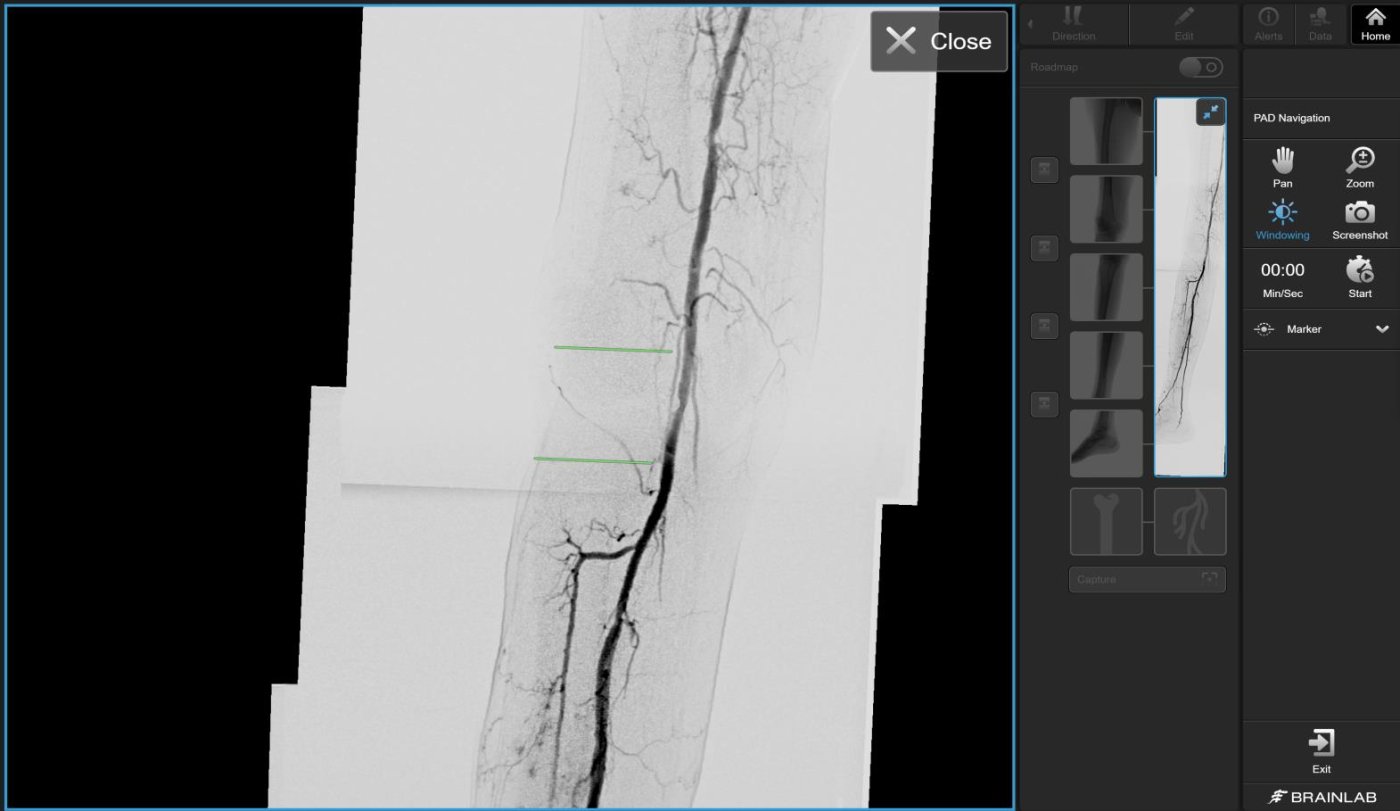

De software combineert vooraf gemaakte angiografiebeelden tot één doorlopende weergave van de vaten. Deze roadmap wordt live als overlay getoond tijdens de procedure, zodat de arts altijd met een compleet overzicht werkt. Het systeem sluit eenvoudig aan op mobiele C-arms en integreert rechtstreeks met PACS voor beeldopslag.

• Volledig overzicht van onderste ledematen en iliacale arteriën in één beeld

• Automatische samenvoeging van beelden voor een continu vatenoverzicht